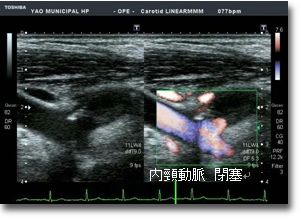

頸動脈エコー

生活習慣病が問題になり、現代社会にてメタボリックシンドロームが注目を集めています。動脈硬化性疾患の発症予防のため、早期の対応が重要と考えられています。頸動脈エコーは全身の動脈硬化の程度を示す一つの指標として、脳血管疾患の評価、また早期の動脈硬化を簡易に評価可能な検査です。検査時間は15分~30分程度です。